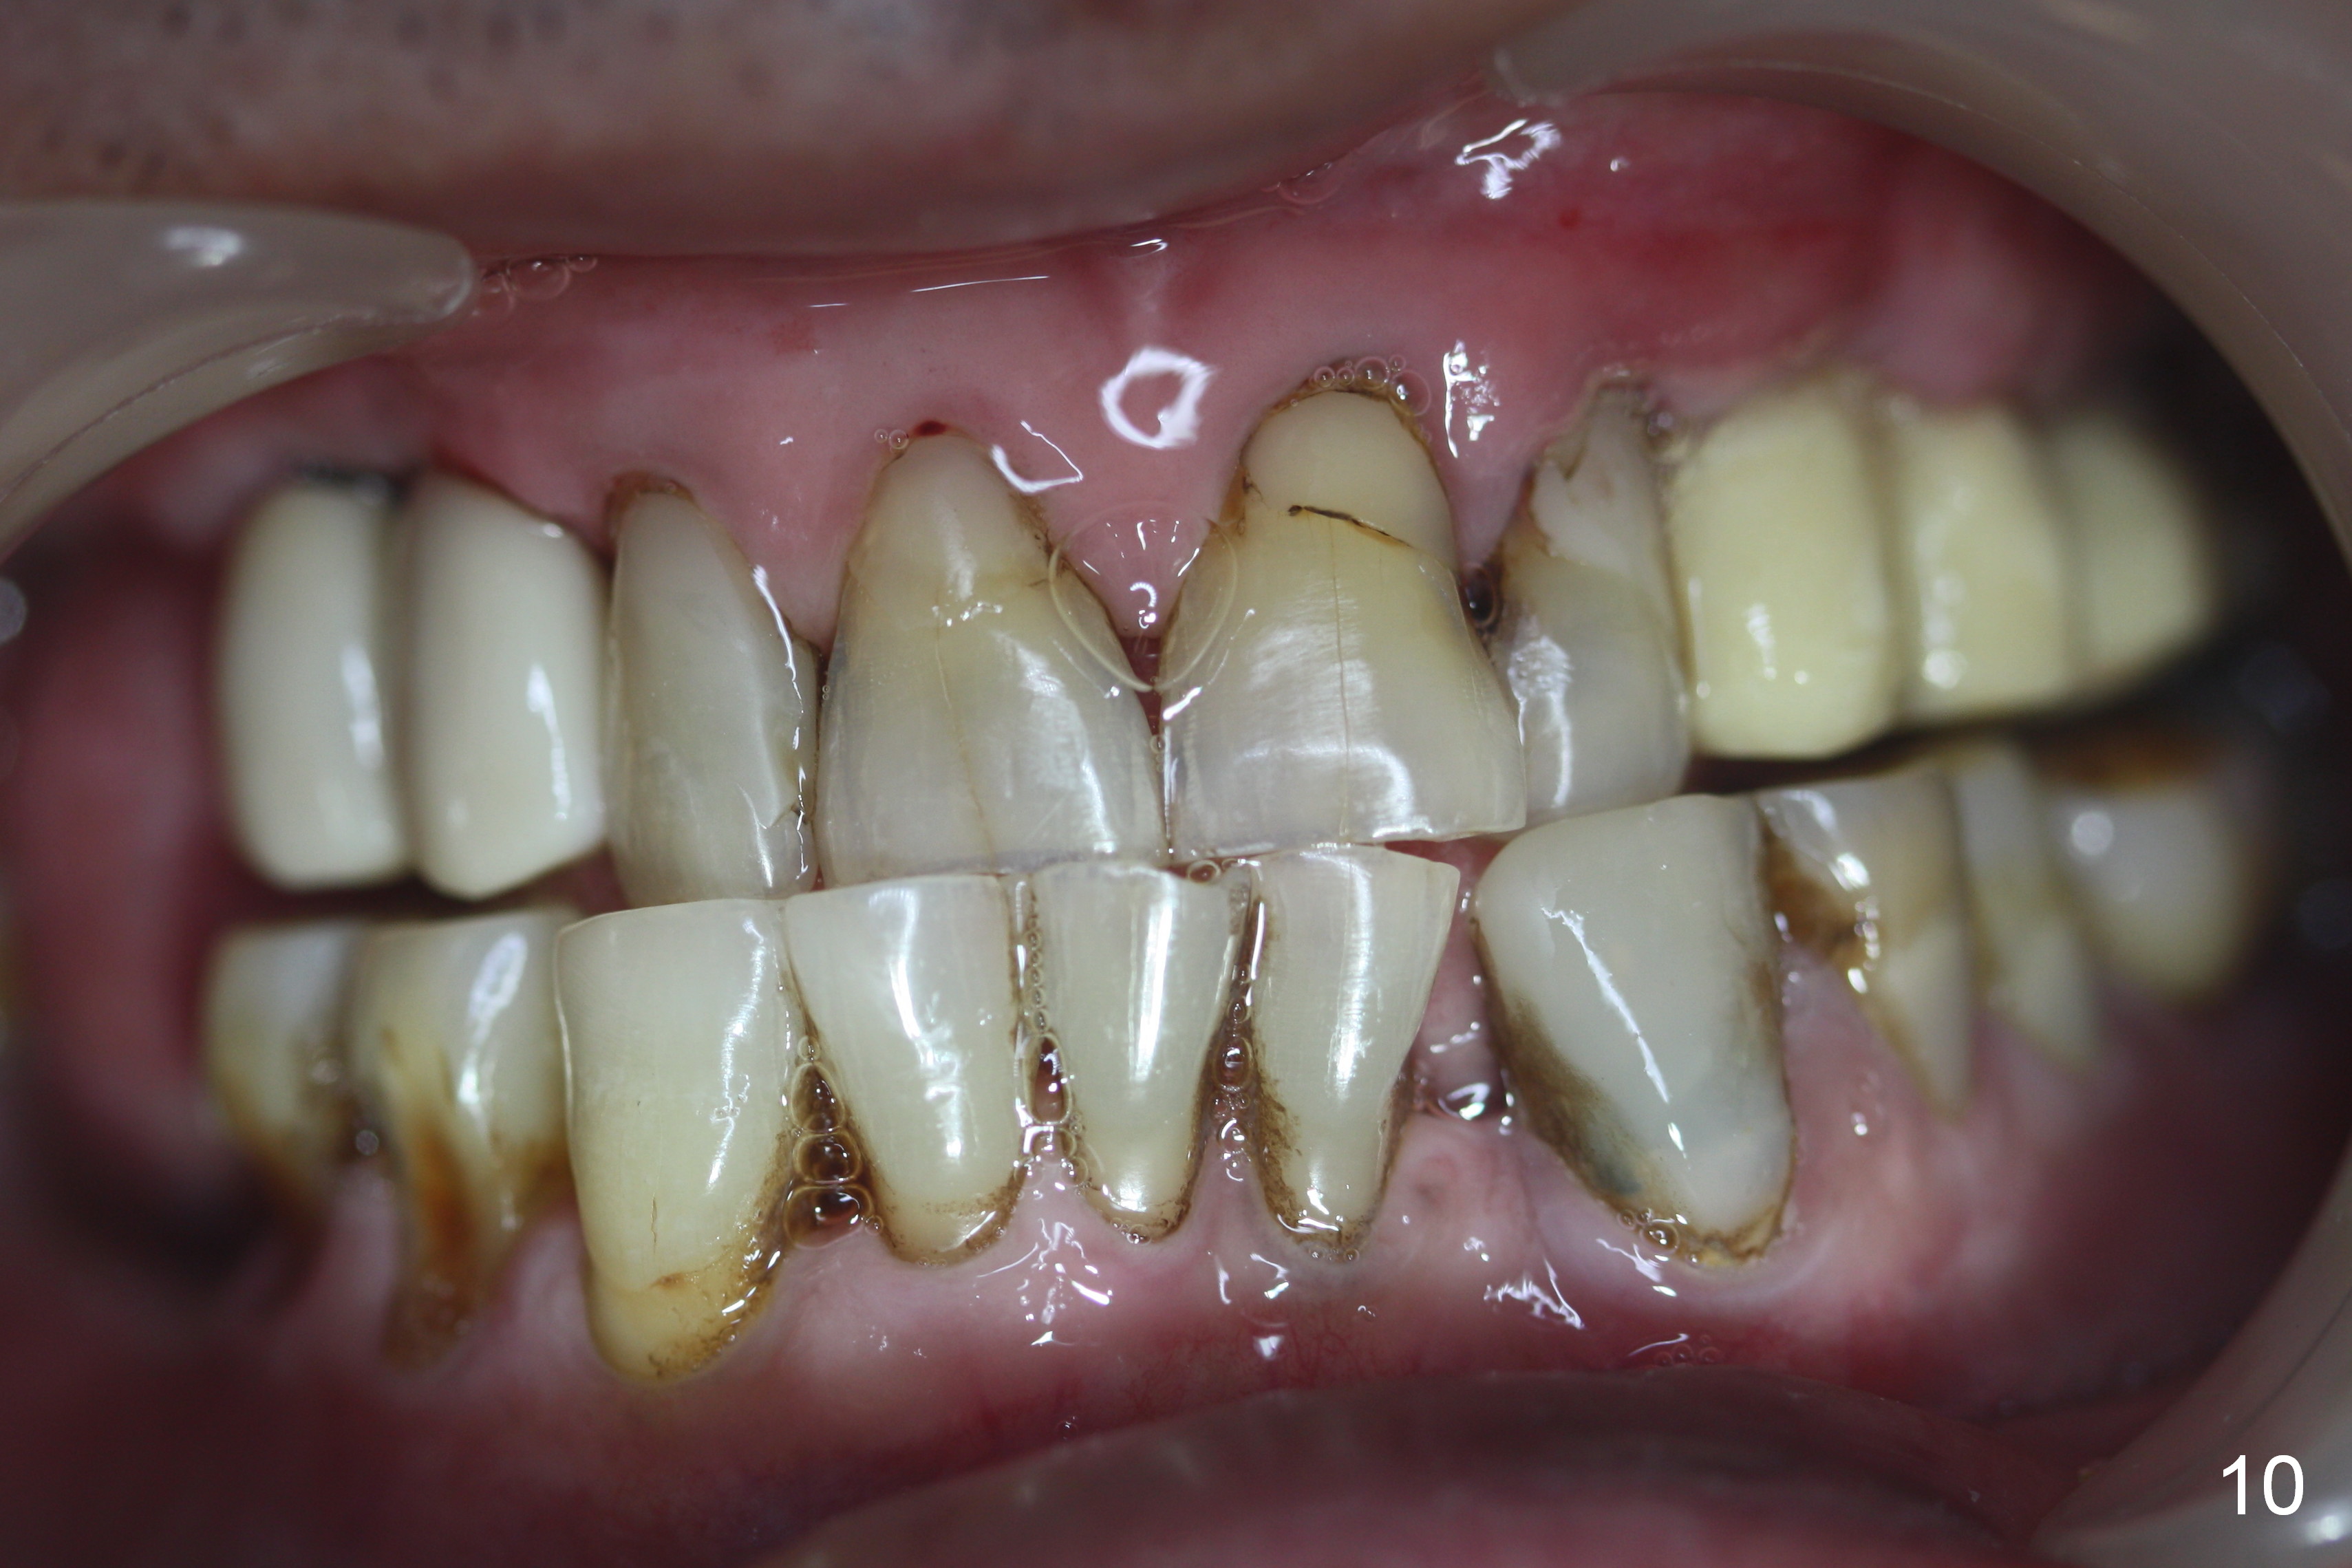

Bone density in the distal gap of #5 appears to have increased 3 months postop (Fig.7).  Prior to definitive restoration cementation (3.5 months postop), the buccal plate does not collapse (Fig.8).  There is no occlusal contact of the new restorations (Fig.9 *), probably due to bite discrepancy (Fig.10,11).